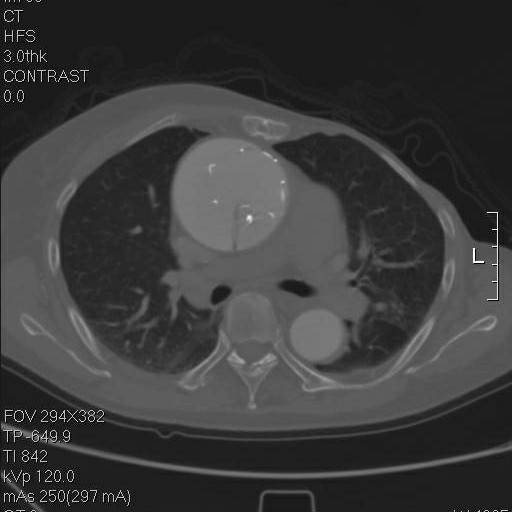

到弓部可以看到,支架远端贴得倒还可以

冠状面重建,方框示头臂干看上去完全开口于假腔,左颈总似乎被支架盖住了